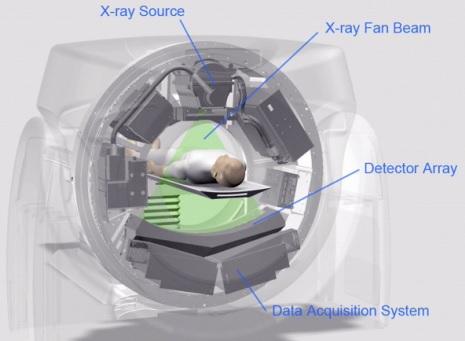

CT stands for Computerized Tomography. This technology uses X-rays. A CT scan machine takes numerous X-ray images from different angles and a computer then constructs a 3D picture of the inside of the body.

The CT scanner features a moving platform (or “cache”) where patients lie in a sleeping position. This platform slowly moves during the scanning process. Typically, two scans are performed: the first captures a general image, and the second provides a more detailed view. A complete CT scan usually takes around 5 minutes.